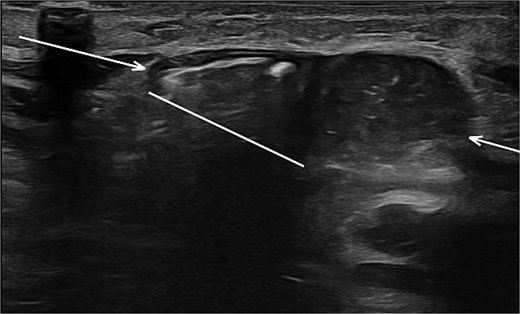

Sonographic imaging of the abdomen revealing a hernia defect (white line) and the hernial sac (white arrows).

Sonographic imaging comparing left and right upper quadrant. On the left side intestinal content is seen within the hernia sac. On dynamic sonography peristalsis was apparent.